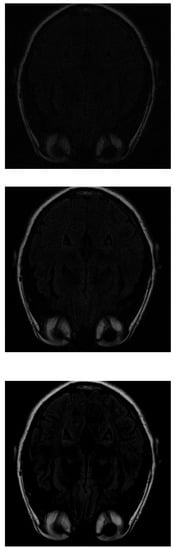

With the PD algorithm, the object is much clearer with lower measurements. With 30% of the initial values (Figure 8 top), the structure inside the head can be recognized and delimited, even if it is of low intensity. As the number of measurements increases, the images obtain better resolution. At 70% (Figure 8 middle), the image is similar to the original. Finally, at 100% (Figure 8 bottom), the gray matter loses its intensity.

Figure 8. Reconstruction of the image in Figure 3 using PD with 30 % (top), 70 % (middle) and 100 % (bottom) of taken measurements.

Mathematics 11 03573 g008